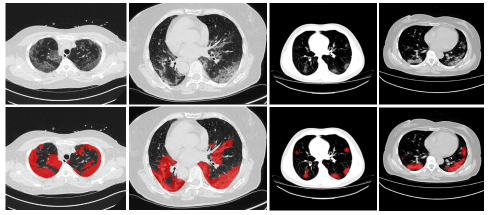

Refer to caption

Figure 1: Examples of COVID-19 infections in CT volumes showing the large variations of shape, size and position of lung infections. The upper row shows the raw images (from axial view) and the lower row shows corresponding annotations of infection areas.

However, the success of deep learning methods mainly requires large amount of high-quality annotated datasets, while it is impractical to collect large amount of well annotated data in real clinical approach, especially when radiologists are busy fighting the coronavirus disease. Additionally, as shown in Fig.1, the large variations in shape, size and position of lung infections and large inter-case variations pose great challenges for the segmentation tasks [17]. Therefore, exploring annotation-efficient COVID-19 lung infection segmentation methods with limited labeled data has become an urgent need especially in the current situation.